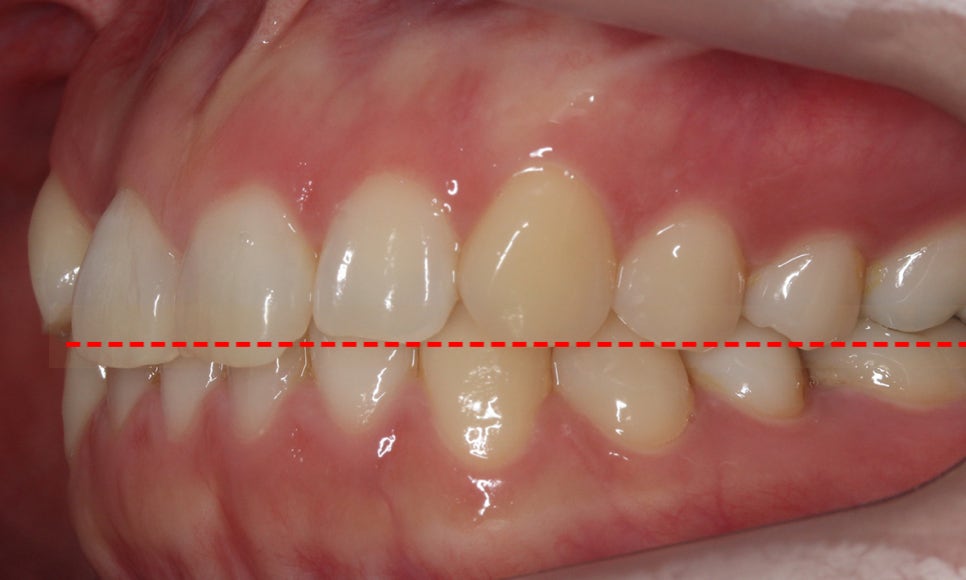

교합평면을 확인해보면 덧니교정 전 구치부에서

전치부까지 치아의 높이가 일정하지 않고

상악 측절치의 경우 설측으로 밀려 들어가서

반대로 교합되고 있는 모습인데요,

안쪽으로 뻐드러진 측절치를 바르게

배열하기 위해서는 구치부 치아들을

뒤로 당겨 공간을 확보한 후 각도를 조정하거나

소구치를 발치하여 치아가 배열될 수 있는

공간을 확보해야 합니다.

반대쪽 교합평면 또한 덧니교정 전

치아의 높이가 일정하지 않고

삐뚤거리는 모습을 확인할 수 있습니다.